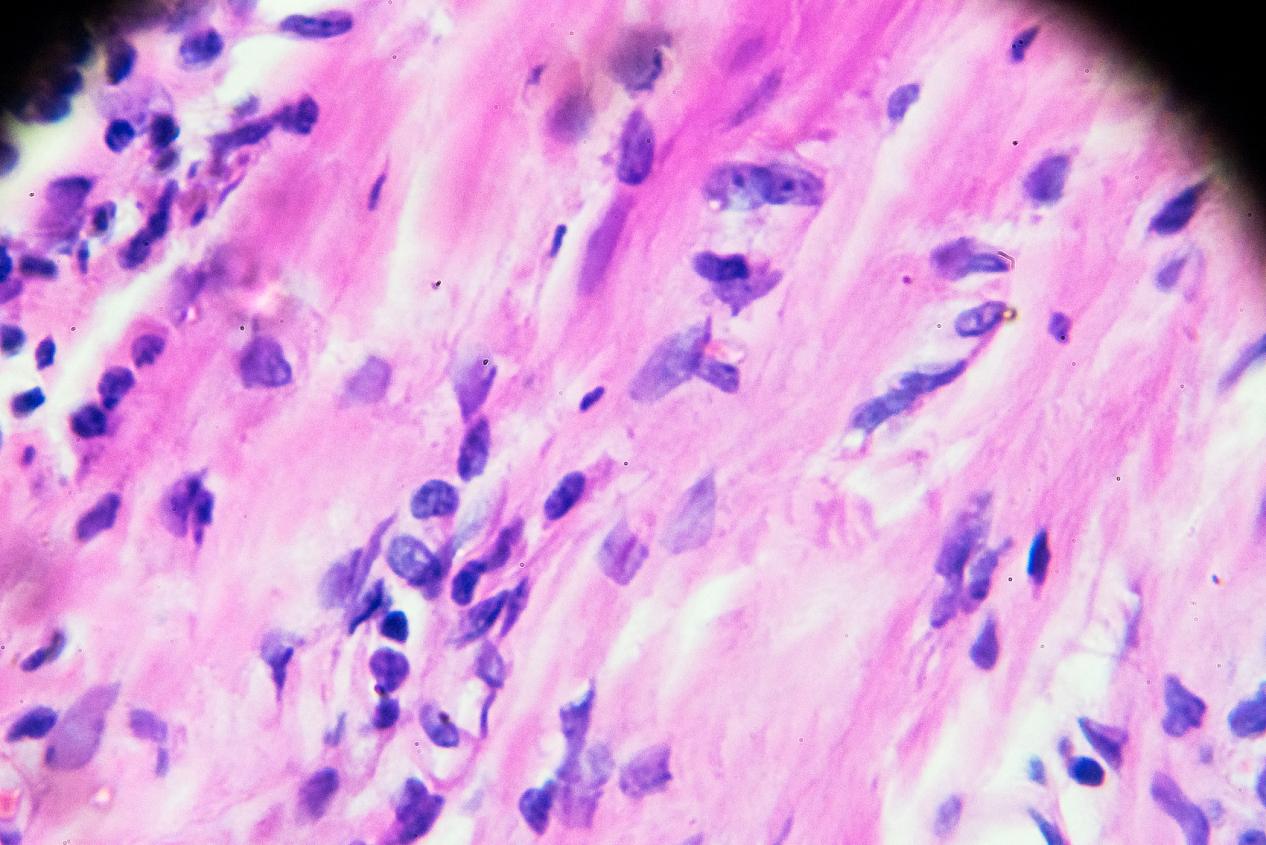

淋巴瘤的临床表现,昆明淋巴瘤医院哪家好-昆明医科肿瘤医院淋巴瘤是一类以淋巴细胞或淋巴组织为起始细胞的肿瘤,其临床表现因患者年龄、病理类型和病变部位等因素而异。以下是淋巴瘤可能出现的一些常见临床表现:淋巴结肿大:淋巴结是淋巴组织的一部分,淋巴瘤的最常见表现之一是...

淋巴瘤的概述,昆明淋巴瘤医院推荐哪家-昆明医科肿瘤医院淋巴瘤是一种源于淋巴系统的恶性肿瘤,它可以发生在身体任何部位的淋巴组织,包括淋巴结、脾脏、骨髓和其他淋巴器官。淋巴瘤是一种比较常见的肿瘤,它可以发生于任何年龄,但是在中年人和老年人中更为常见。淋巴瘤是由淋巴...

淋巴瘤的发病机制,昆明淋巴瘤医院排名哪家好-昆明医科肿瘤医院淋巴瘤是一种由淋巴细胞或浆细胞发生恶性转化导致的恶性肿瘤。淋巴瘤的发病机制是一个复杂的过程,涉及到多种因素的相互作用。本文将介绍淋巴瘤发病的几种常见机制。染色体异常染色体异常是淋巴瘤发生的常见机制之一...

淋巴瘤的病因,昆明淋巴瘤医院哪家好-昆明医科肿瘤医院淋巴瘤是一种由淋巴细胞或浆细胞发生恶性转化导致的恶性肿瘤。目前对于淋巴瘤的具体病因仍不是完全清楚的,但是已知有一些可能的因素会增加淋巴瘤的发生风险。免疫系统异常:免疫系统的异常功能可能会导致淋巴细胞的不正常增...